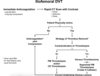

How do you investigate and manage a DVT in general terms?

Ix

- Swollen hot limb with pain localised to calf

- Calculate Well’s score, if 2 or more do US Doppler

- If <2 do D-dimer

Mx

- Start apixaban or rivaroxaban for 3-6 months. If Cx start LMWH for 5 days first then switch to dabigatran for 3 months

- If iliofemoral DVT then urgent vascular review